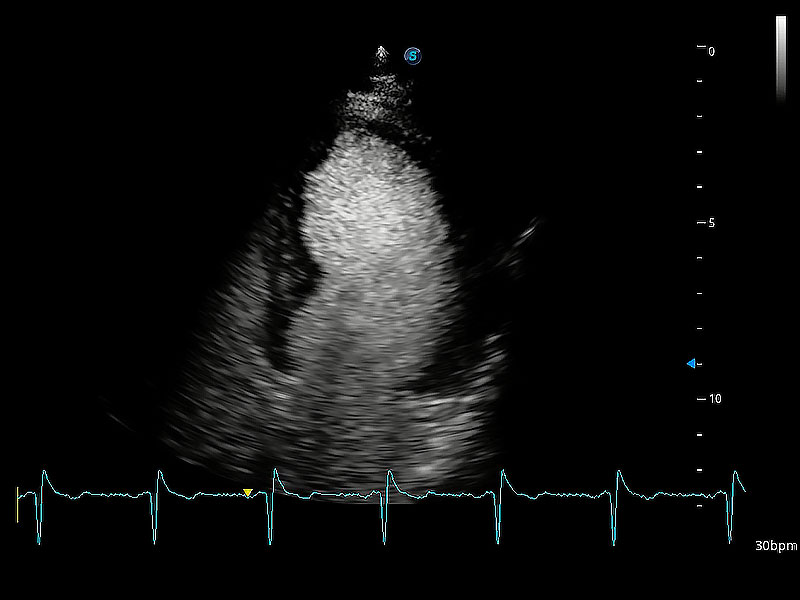

ProPet 80 配備了豐富的心臟探頭群、先進(jìn)的成像技術(shù)和專業(yè)的心臟測(cè)量工具,可幫助動(dòng)物醫(yī)生為不同體型和生理結(jié)構(gòu)的動(dòng)物提供心臟和心肌功能的全面評(píng)估。

實(shí)時(shí)用顏色表示心肌組織運(yùn)動(dòng),觀察和定量組織的運(yùn)動(dòng)情況,對(duì)快速檢測(cè)與評(píng)估心肌的灌注和活性、電傳導(dǎo)及心肌收縮和舒張功能等均能提供重要的診斷信息。

通過(guò)心肌識(shí)別技術(shù)與二維斑點(diǎn)追蹤技術(shù)相結(jié)合,對(duì)心臟的超聲圖像進(jìn)行量化分析。計(jì)算心肌17個(gè)節(jié)段的應(yīng)變、應(yīng)變率、速度、位移等,并通過(guò)牛眼圖的形式進(jìn)行呈現(xiàn)。

通過(guò)360度任意調(diào)節(jié)3條M型取樣線,在同一心動(dòng)周期上觀察心臟不同位置的運(yùn)動(dòng)曲線,得到準(zhǔn)確的心功能測(cè)量數(shù)據(jù),有效評(píng)估心肌運(yùn)動(dòng)及左心室功能。